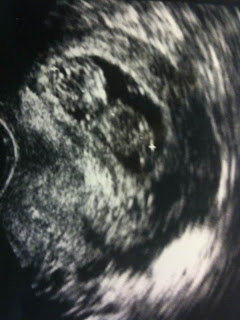

Kira and Coco are both doing great. Kira had her 32-week check-up yesterday (Friday, December 18th) and both she and Coco are excellent. At the last appt. (at 30-weeks), Coco was still in a breech position (meaning head up, not down as is preferred for birth). That is not that unusual but we were all praying that she would turn soon because if she stayed in a breech position we would most likely have to have a c-section delivery. (Usually babies turn into the heads down position sometime around 30 weeks.) We were thrilled to find out yesterday that Coco has turned and is now in the head down position! Yippee! Also, at the last appt. Coco was a bit camera shy so we didn't get a lot of good shots but yesterday she was camera ready and we got some incredible pictures of her adorable face. I know, we're probably biased but she is gorgeous! Take a look for yourself!